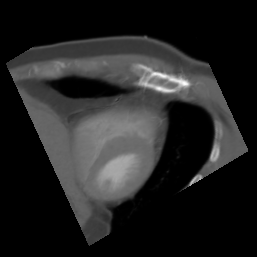

4.2.3 External Generalization Validation

To further validate the generalization ability of our proposed method, we similarly select four query images (2C, 4C, Y, and RV1) and conduct experiments on 20 target CT volumes from Dataset 2. Table 3 also shows the average quantitative results of the optimization-based method Opt-SVR, the learning-based method Lea-AVP, and our proposed framework AVP-AP. As we can see, our method outperforms the traditional Opt-SVR, and the SSIM metric is 3% better than Lea-AVP on the 4C plane. Furthermore, Fig. 6 visualizes the positioning results in three different CT volumes (CT1, CT2, CT3), where the query images are resampled from CT1. We can see that although the query images originate from CT1, our framework AVP-AP can effectively position similar slices in CT1, CT2, and CT3. This indicates that our framework has better generalization capability, and the query images can come from any different CT volume.

(a) 2C

(b) 4C

(c) Y

(d) RV1

(e) RV2

(f) RV3